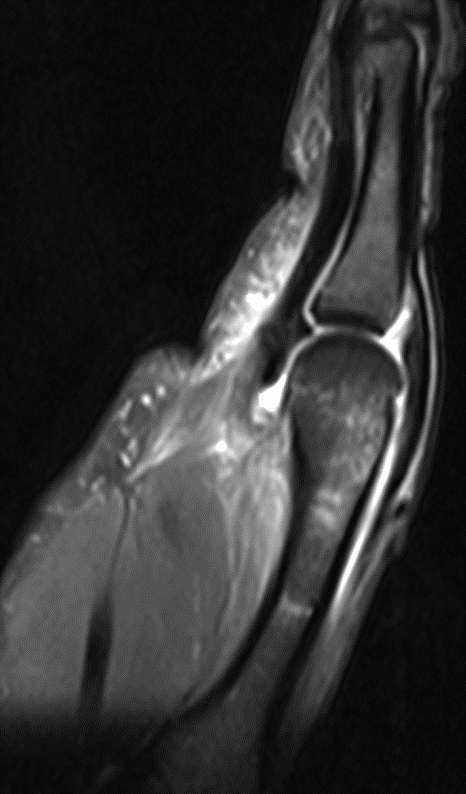

Результат МРТ правого лучезапястного сустава (рис. 2), подтвердил клиническое предположение о повреждении ладьевидно-полулунной связки, который заключался в нарушении целостности структуры связки. Также были выявлены признаки асептического некроза ладьевидной кости в стадии отека костной ткани.

Рис. 2. МРТ-исследование правого лучезапястного сустава. Получены протон взвешенные изображения с подавлением сигнала от жировой ткани (PD FAT SAT) в аксиальной, сагиттальной и фронтальной плоскостях, Т1 взвешенные изображения во фронтальной плоскости. На полученных сканах определяется: 1 – увеличение ладьевидно-полулунного сустава вдвое по сравнению с соседними; 2 – вдоль оси ладьевидной кости отмечается скопление жидкости, что можно расценить, как продольный перелом ладьевидной кости, либо отек костной ткани

После операции лучезапястный сустав фиксировался иммобилизационной повязкой сроком на 4 недели. По окончанию срока иммобилизации пациентке была рекомендована постепенная разработка лучезапястного сустава, исключающая осевые нагрузки. Через 6 недель с момента операции пациентке было выполнено МРТ исследование для осуществления контроля положения восстановленной связки (рис. 5).

Рис. 5. МРТ исследование правого лучезапястного сустава. На МРТ сканах во фронтальной плоскости: 1) отмечается восстановление пространства между ладьевидной и полулунной костями, отчетливо видна связка; верифицируется биодеградируемый пин и якорный фиксатор в ладьевидной кости; 2) отмечается синовит лучезапястного сустава и отсутствие отека костной ткани ладьевидной кости